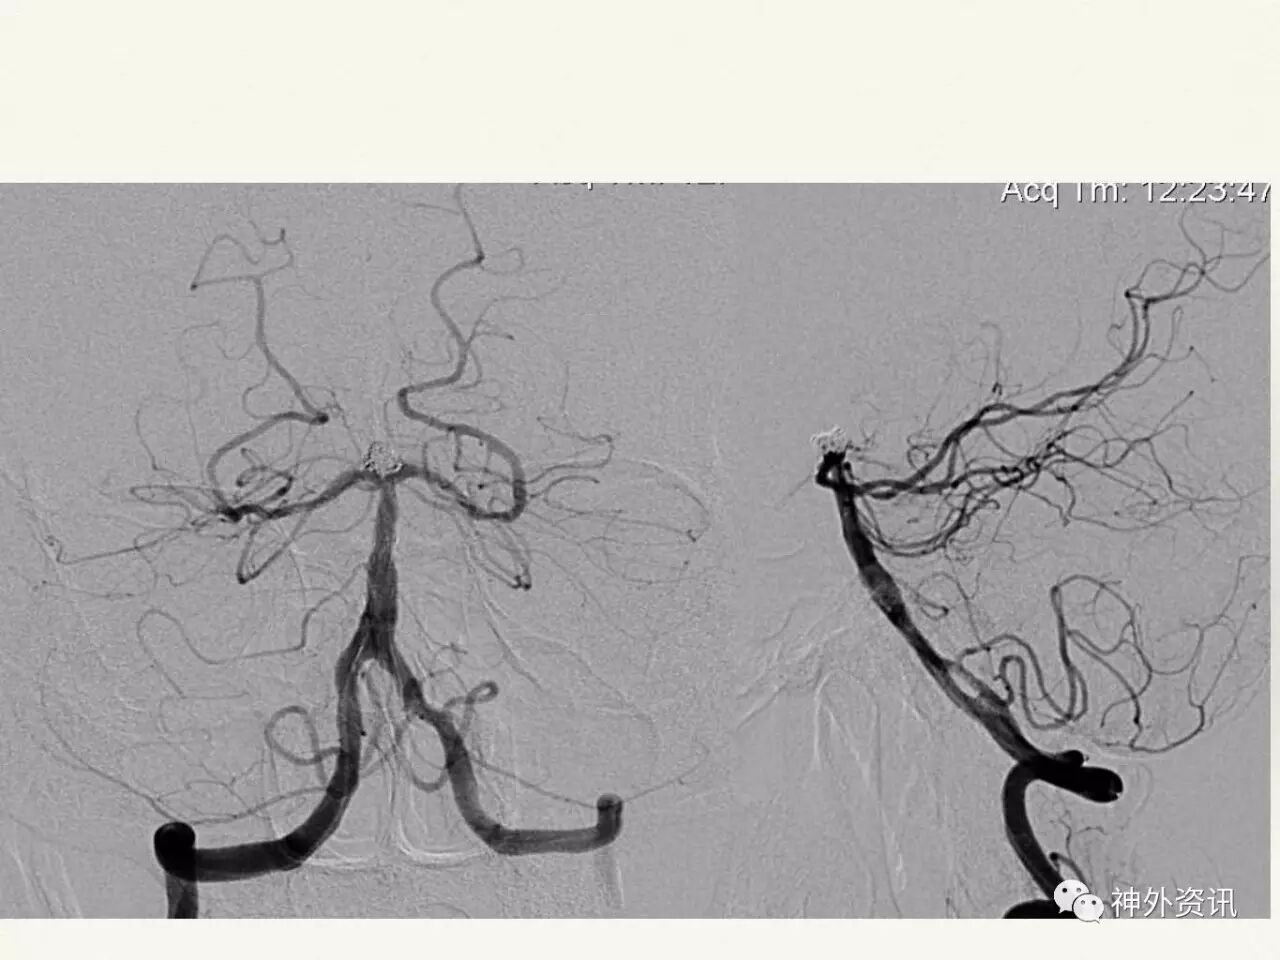

在东北地区率先开展了颈内动脉、大脑中动脉及基底动脉闭塞血管内再通、颅内动脉栓塞急性期取栓、血流导向装置治疗大型宽颈动脉瘤等,对颅内动脉瘤、动静脉畸形、颈动脉及颅内动脉狭窄、颈内动脉海绵窦瘘、硬脑膜动静脉瘘等外科治疗具有较深的造诣。完成脑血管造影8600余例,各类脑血管病介入手术共4500余例,动脉瘤、动静脉畸形、脑肿瘤、脑出血及脑外伤等外科手术1500余例。